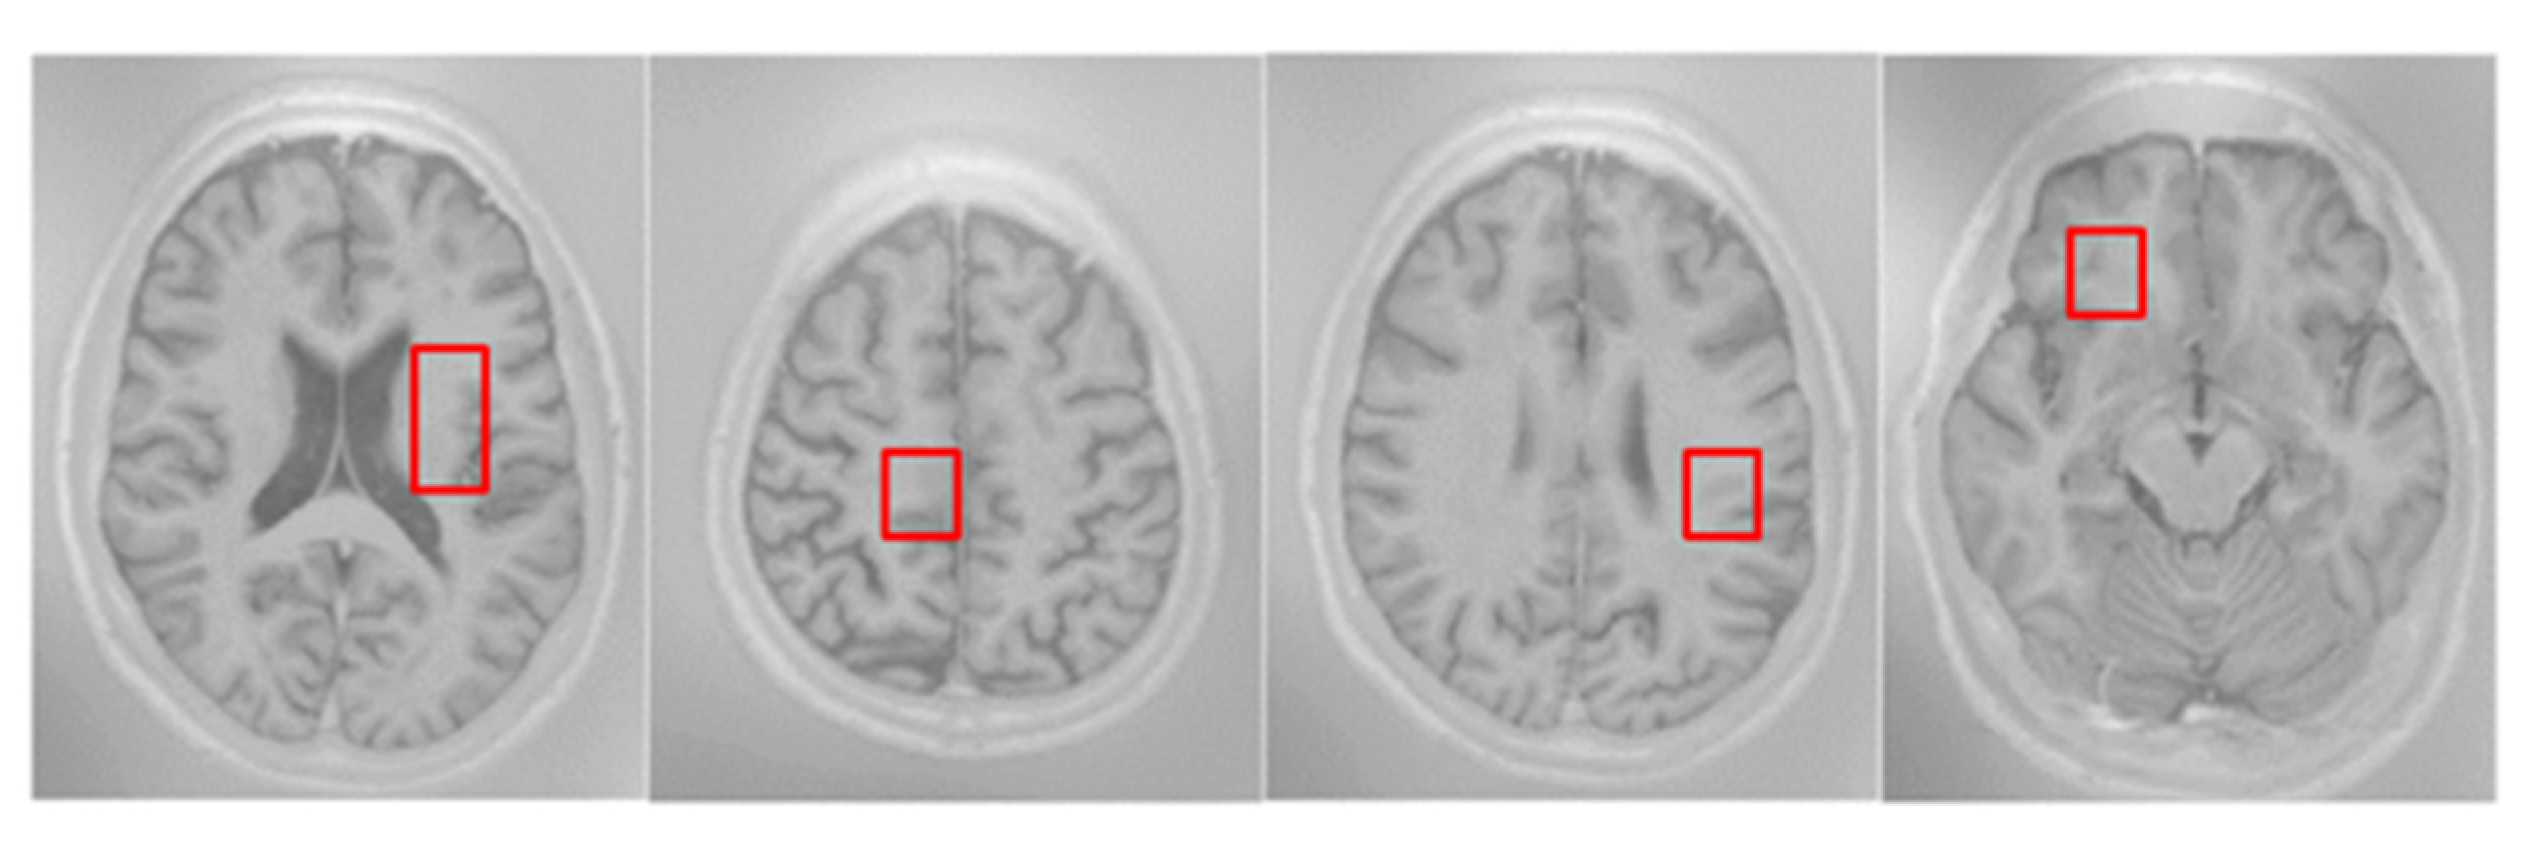

3.5. Dataset Introduction